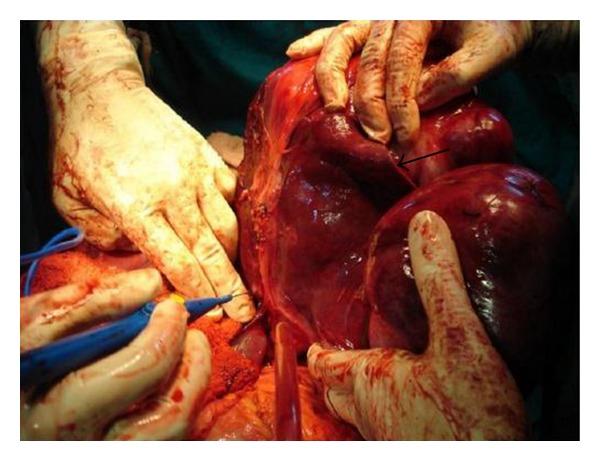

We report an unusual presentation of a sporadic intra-abdominal desmoid tumour, possibly arising from the diaphragm, masquerading as a hepatic mass in a young female without any history of surgery or trauma. Histopathology ruled out a hepatic origin of the tumour as was inferred from pre- and intraoperative evaluation. Immunohistochemistry showed positivity of lesional fibroblastic cells for β-catenin and negativity for CD34, CD117, EMA, SMA, desmin, vimentin, cytokeratin, and ALK1 thereby confirming the diagnosis of a desmoid tumour. There exist only a few reports in the literature on desmoids related to the diaphragm, but only one on a diaphragmatic desmoid that is possibly primary.

我们报告了一例散发性腹腔内硬纤维瘤的罕见表现,该肿瘤可能起源于膈肌,在一名无手术或外伤史的年轻女性中伪装成肝脏肿块。组织病理学排除了肿瘤起源于肝脏,这一点在术前和术中评估中已得到推断。免疫组织化学显示病变的成纤维细胞β-连环蛋白呈阳性,而CD34、CD117、EMA、SMA、结蛋白、波形蛋白、细胞角蛋白和ALK1呈阴性,从而确诊为硬纤维瘤。文献中关于与膈肌相关的硬纤维瘤的报道很少,而关于可能是原发性的膈肌硬纤维瘤的报道仅有一例。